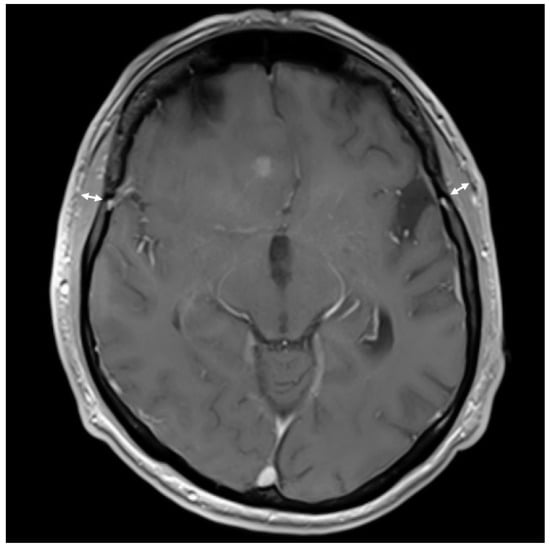

2.2. TMT Measurement